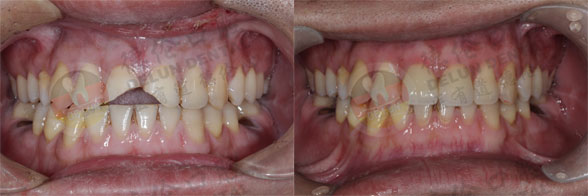

美容冠修复案例

查看更多德伦口腔美容冠修复案例>>>